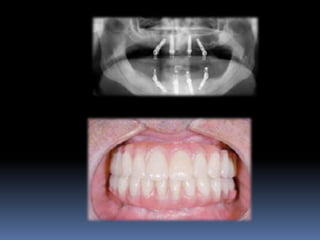

Exames Imaginológicos

Radiografias periapicais, telerradiografias e

panorâmicas;

Tomografias computadorizadas

Softwares de imagens 3D